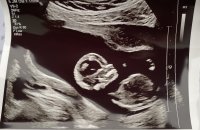

En liten gutt koser seg og vokser inni magen min.Vi fikk til og med se den lille hikke. Han klarte ikke ligge i ro et sekund, så godt å se at han er aktiv, sprellet med beina og vinket til oss! :D Ingen tegn til noe avvik eller kromosomfeil, så fantastisk godt å høre at lille ser frisk ut. CRL 9 cm :Heartblue sjekk siste bilde, der ser man rumpa og den lille saken som stikker ut:joyful: